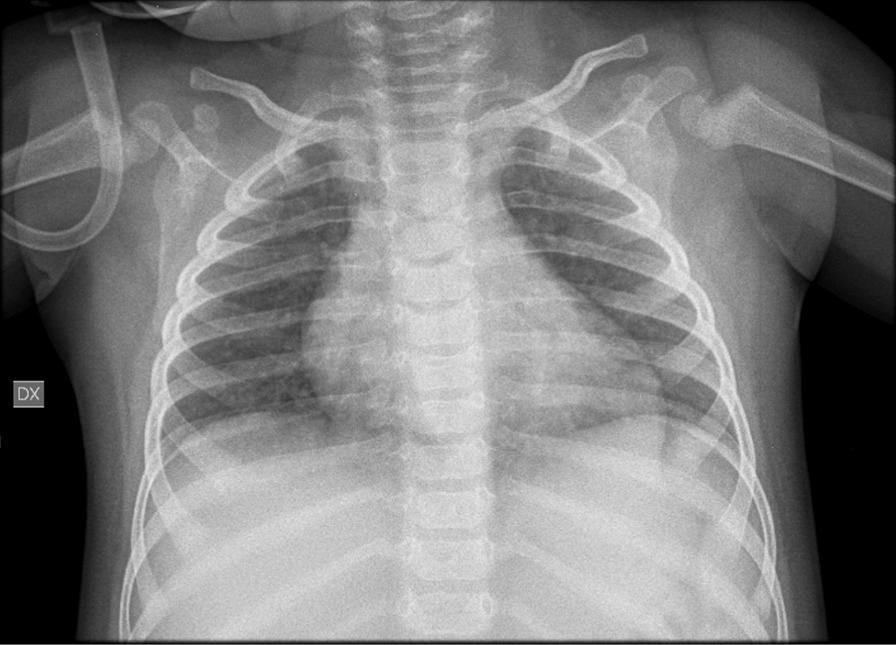

We describe a 14-month-old boy, with a previous diagnosis of propionic acidemia (PA) by expanded newborn screening, who, admitted for a suspected metabolic crisis, tested positive for SARS-CoV-2. Since propionic acidemia was diagnosed, the patient has followed the recommended diet for this inborn error of metabolism. Although propionic acidemia patients are at a high risk of suffering metabolic crises, frequently associated with permanent clinical complications, psychomotor development of this patient was normal. The SARS-CoV-2 infection (at about 1 year of age) caused the patient's first metabolic crisis. However, his clinical course was in keeping with a mild clinical form of COVID-19, and he recovered without experiencing severe clinical consequences. We describe this patient in order to improve the knowledge about follow up of PA patients identified by newborn screening and to increase the limited number of reports of SARS-CoV-2 infection in children with comorbidities, especially inborn errors of metabolism.

我们描述了一名 14 个月大的男孩,曾通过扩大的新生儿筛查诊断为丙酸血症(PA),因疑似代谢危象入院,新冠病毒检测呈阳性。自丙酸血症确诊以来,患儿一直遵循这种遗传性代谢缺陷的推荐饮食。尽管丙酸血症患儿有发生代谢危象的高风险,且常伴有永久性临床并发症,但该患儿的精神运动发育正常。新冠病毒感染(约 1 岁时)导致患儿首次发生代谢危象。然而,他的临床过程与 COVID-19 的轻度临床形式一致,且未出现严重临床后果而康复。我们描述这名患儿的情况,旨在提高对通过新生儿筛查发现的丙酸血症患儿的随访知识,并增加患有合并症(尤其是遗传性代谢缺陷)儿童中新冠病毒感染的有限报告数量。